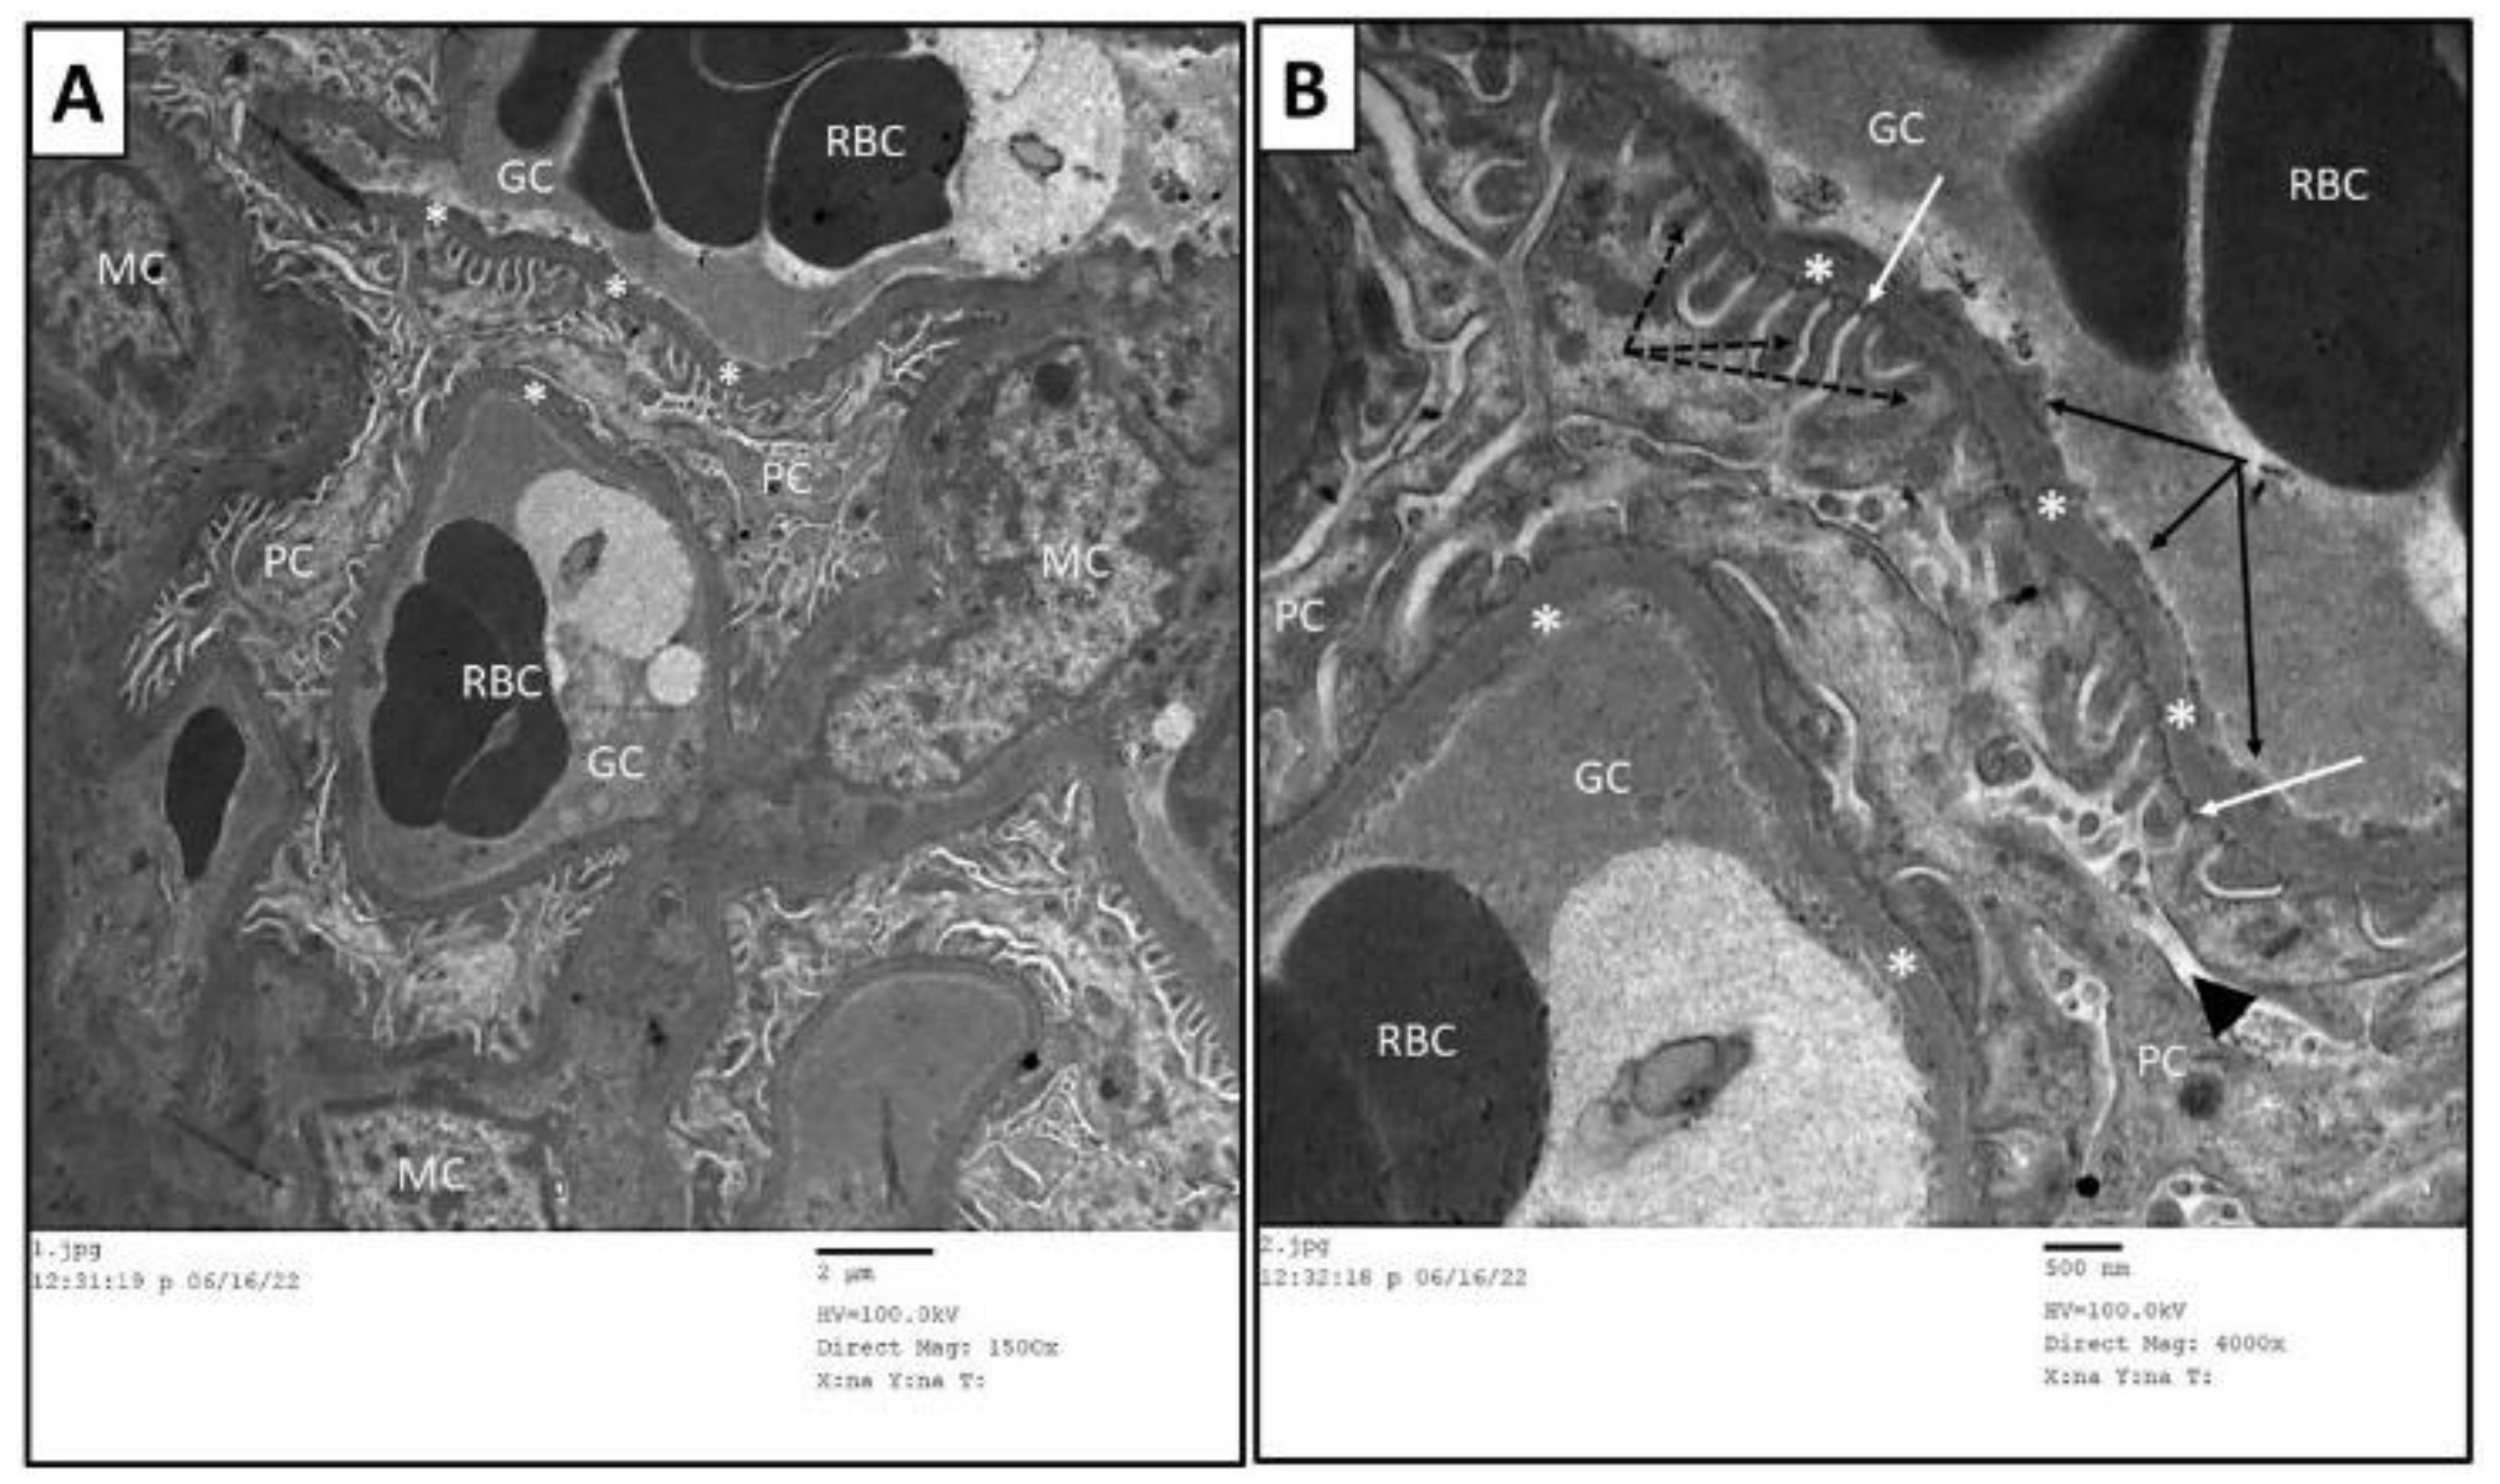

3.6. Ultrastructure Assessment of Renal Tissue